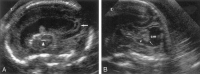

Background and purpose: Congenital cytomegalovirus (CMV) infection can cause a wide range of brain anomalies. These changes have been well described postnatally, but descriptions of their in utero evolution are scarce. The purpose of this study was to analyze the sonographic spectrum of intracranial abnormalities in fetuses with proved CMV infection and to determine characteristic patterns of this infection.

Methods: We reviewed the transabdominal and transvaginal sonograms of eight fetuses with proved CMV infection. The sonographic analysis searched for signs of ventriculitis, leukomalacia, calcification, vasculitis, and periventricular cyst formation. The gyral pattern, corpus callosum, and cerebellar morphology also were examined. Fetal MR imaging was performed in two cases.

Results: The sonographic diagnosis of suspected CMV infection was made at a mean gestational age of 27.5 weeks (range, 22-37 weeks). An abnormal pattern of periventricular echogenicity was found in all fetuses. Echogenic intraparenchymal foci and ventriculomegaly were present in five fetuses. Other signs of fetal infection were intraventricular adhesions, periventricular pseudocysts, sulcation and gyral abnormal patterns, hypoplastic corpus callosum, cerebellar and cisterna magna abnormalities, and signs of striatal artery vasculopathy. For all fetuses, transvaginal sonography provided additional information. Fetal MR imaging provided additional information in one case.

Conclusion: The presence of the described sonographic findings, particularly if two or more are present in the same fetus, is an indication for CMV investigation.